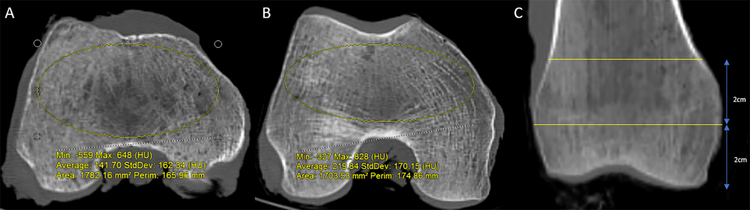

The specimens underwent standard clinical Discovery CT750 HD CT scans (General Electric, Madison, WI). Picture Archiving and Communication Systems (PACS) was used for measurements. Cortical width (the linear distance between the outer edges of the femoral cortex) and cortical index (the ratio of the sum of the medial and lateral cortical width divided by the entire width of the bone) were measured at two levels within the distal femur (Fig. 1). Measurements were performed three times by one author (JTB) and averaged. The locations (i.e., 2 and 4 cm proximal to the most distal point of the distal femoral condyles) were chosen to represent two locations of screw clusters in a standard distal femoral locking plate. HU were obtained on axial CT slices at the same two levels in the distal femur. An elliptical region of interest (ROI) was drawn as large as possible without including the cortical bone (Fig. 2).

Fig. 1

Representative measurements of cortical width and cortical index on a mid-coronal CT image of the distal femur. Measurements are made at 2 and 4 cm proximal to the most distal aspect of the bone

Fig. 2

Elliptical region of interests to measure CT HU drawn on axial CT slice 4 cm (A) and 2 cm (B) proximal to the end of the femur. Coronal CT (C) shows the levels of the axial slices